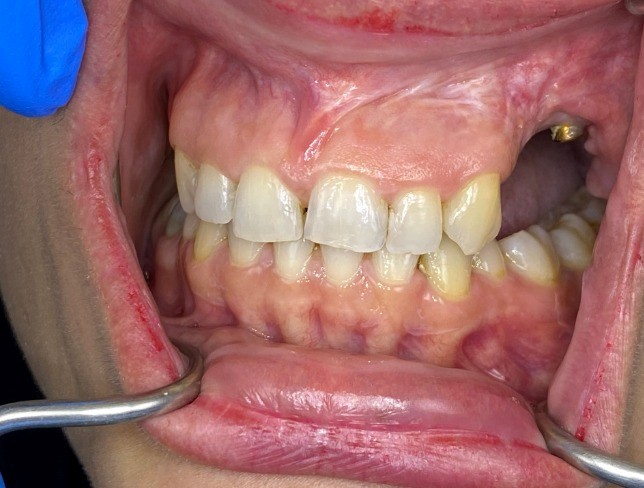

Post-operative imaging (Image 3) confirmed stable implant integration, and the patient underwent prosthetic rehabilitation with a fixed implant-supported prosthesis (Images 4, 5, and 6). Follow-up assessments showed optimal occlusion, favorable gingival adaptation, and high patient satisfaction.

Following distraction, the post-distraction radiograph (Image 2b) reveals successful vertical bone elongation. The post-implant and prosthesis image (Image 3) further demonstrates ideal implant placement and successful prosthetic integration. Intraoral photographs (Images 4 and 5) depict the final fixed prosthesis with harmonious gingival contours and alignment, while the frontal occlusion view (Image 6) confirms esthetic and functional restoration. The entire workflow from device installation to final rehabilitation is supported by radiographic and clinical validation.

Fig 4: 1. Frontal Intraoral Image: Healthy gingival margins and anterior occlusion.